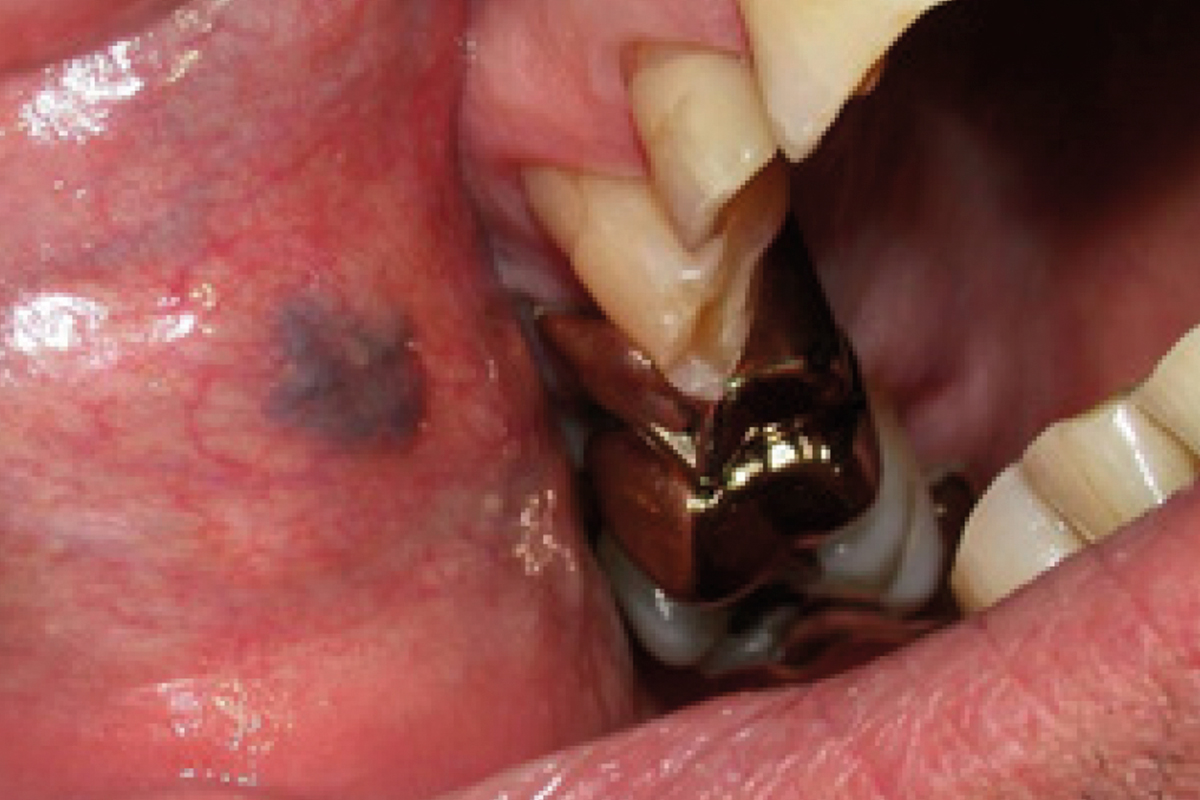

TRAITEMENT HÉMANGIOME DANS LA CAVITÉ ORALE